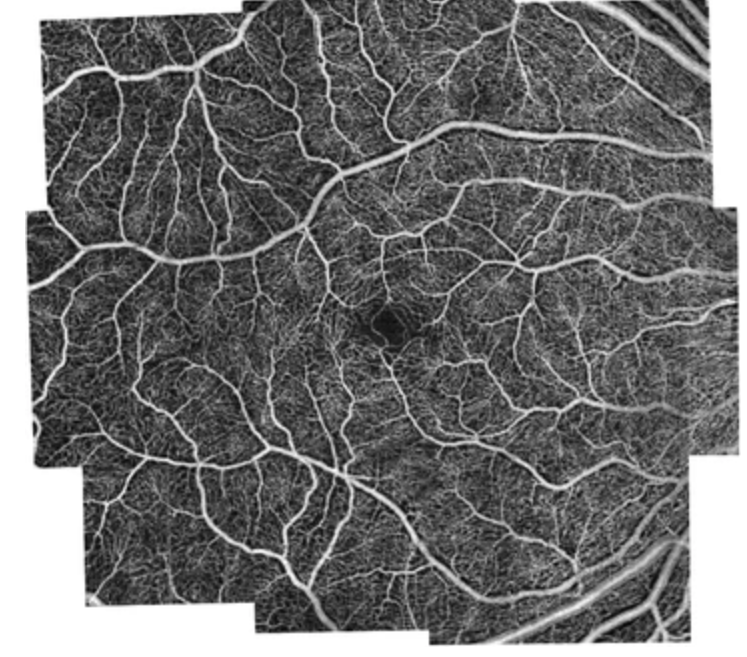

- 光学相干断层造影(OCTA / FFA)

OCTA:

OCTA (Optical Coherence Tomography Angiography):

- 用途:OCTA是OCT的一种进阶形式,能够以无需染色剂的方式展现眼睛内部的血流和血管结构。

- 优点:OCTA对于观察视网膜和脉络膜的血管病变非常有用,尤其是在诊断和监测糖尿病视网膜病变、视网膜静脉阻塞等疾病的血管变化。